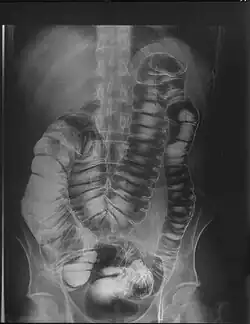

Megacólon - Exame Radiológico com Clister Opaco em Duplo Contraste

Megacólon é um transtorno intestinal caracterizado por dilatação anormal do intestino grosso, definida em um adulto como mais de 12cm de diâmetro no ceco, maior que 8cm no cólon ascendente ou descendente ou 6,5cm no cólon sigmoideo ou reto. [1]